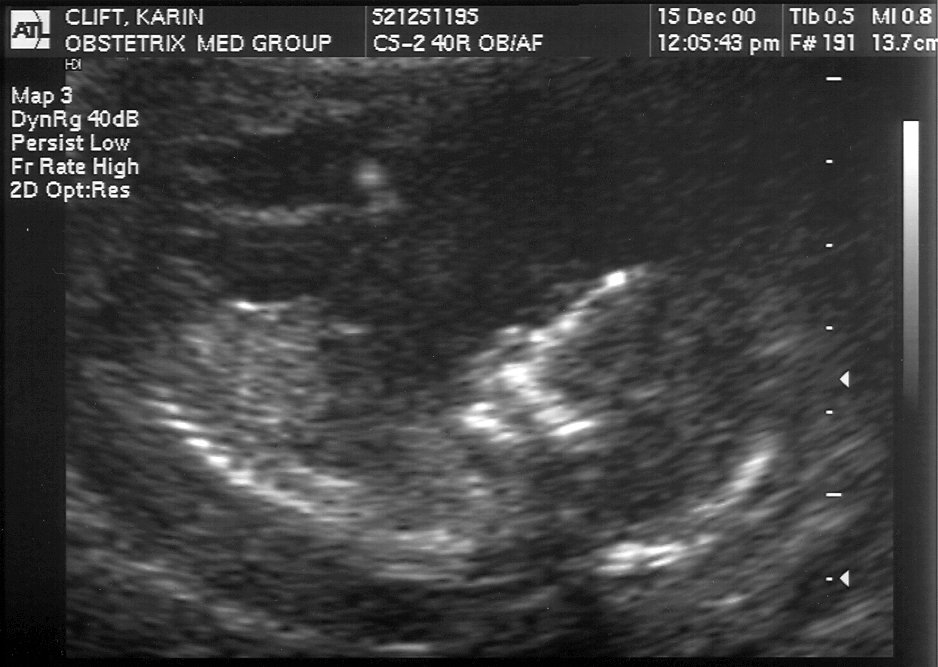

December 15 Amniocentesis results: NORMAL and HEALTHY #1, #2